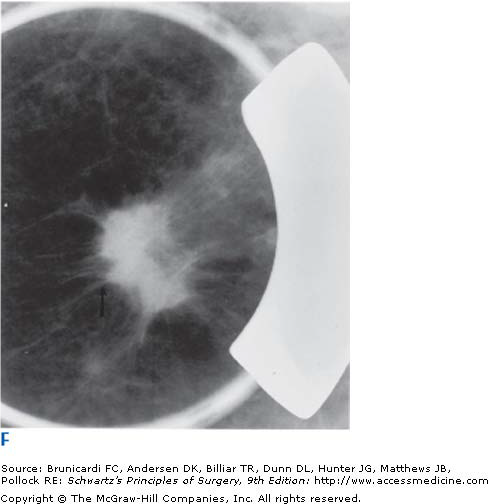

Meme kanserinde 20 yaşından sonra 41 yaşına kadar her kadın periodik olarak her yıl kontrol edilmelidir ve meme us ile kontrol edilip memede kitle olup olmadığı bu kitlenin kistik veya solit olup olmadığı solit kitleninde maliğn özellik taşıyıp taşımadığı saptanmalı, maliğn özellik taşıyorsa biopsi yapılmalıdır. 41yaşından büyük hastalarda ise meme us’na a mamografi ilave edilmelidir. Mamografi yapılamayan hastalarda meme MR tanıda yardımcı olmakta maliğn şüpheli vakalarda biopsi uygulanmaktadır.

* Meme biopsisi ile kesin tanı konur. (Açık biopsi – true – cut iğne biopsisi- bilgisayar işaretleme ile yapılan biopsi).